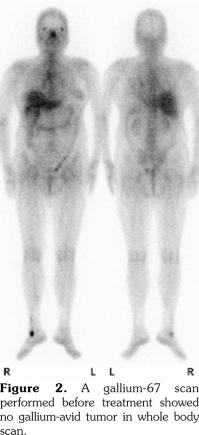

A 53-year-old female patient suffered from pain over most of her body, particularly the joints and the throat. In addition, skin rashes on the trunk without pruritus were noted. She had visited the Rheumatology, Neurology, and Orthopedic Outpatient Department several times. A chest computed tomography (CT) was performed which revealed multiple lymphadenopathies over cervical, mediastinal, and axillary areas. A positron emission tomography (PET)/CT revealed increased fluorine-18-deoxyglucose (FDG) uptake in many lymph nodes including the bilateral neck, axillae, mediastinum, bilateral pulmonary hili, abdominal paraaortic region, iliac regions, and inguinal regions as well as the bone marrow and the spleen (Figure 1). In addition, mild and diffuse increase of FDG uptake in the bone marrow was noted. Lymphoma was suspected first. After discussing with the patient, thoracoscopic mediastinal lymph node biopsy was performed. Fifteen lymph nodes were taken and the results showed histiocytic infiltration in sinusoid area and anthracotic pigment deposition. Reactive lymphoid follicle hyperplasia and focal fibrocalcified nodule formation were also noted. No tumor cell was seen. Gallium-67 (Ga-67) scan was conducted and no gallium-avid tumor was seen throughout the whole body (Figure 2). The laboratory data were negative for antinuclear antibodies, rheumatoid factor- immunoglobulin M, and extractable nuclear antibody, while alanine aminotransferase was high. The final diagnosis was AOSD. In our case, there were no symptoms or signs of either high fever or debilitating joint although the FDG PET showed multiple FDG-avid lesions in the whole body scan. According to the experience of our rheumatologists, methylprednisolone (Metisone) 4 mg/day and non-steroidal anti-inflammatory drugs were prescribed initially and the response to treatment was good. Six months later, the follow- up PET/CT showed complete remission of the FDG-avid lesions seen in the previous PET/CT (Figure 1) and the patient’s symptoms relieved. A written informed consent was obtained from the patient.

In this study, we present the FDG PET/CT and Ga-67 scan findings of a patient who met the Yamaguchi classification criteria for AOSD. The FDG PET/CT scan was not helpful in diagnosing AOSD in this case since lymphoma could not be ruled out. However, the FDG PET/CT scan results were useful for evaluating the distribution and severity of the disease. A negative Ga-67 scan could be beneficial as it would exclude lymphoma. After the diagnosis of AOSD was established, the patient received nonsteroidal anti-inflammatory drugs and glucocorticoids with a good response. Disease activity and therapeutic response were monitored by FDG PET/CT and the findings of a scan performed six months after treatment were negative.(13)

The treatment of AOSD remains largely empirical, relying so far on a few prospective or retrospective studies and not on double- blinded randomized trials with suitable sample sizes.(12) In our case, there were no symptoms or signs of high fever, debilitating joint or life- threatening complications although the FDG PET showed multiple FDG-avid lesions in the whole body scan. According to the experience of our rheumatologists, low dose of corticosteroids was prescribed first and the response to treatment was good. The patient’s symptoms and signs relieved and the follow-up PET/CT showed complete remission of these FDG-avid lesions six months later.